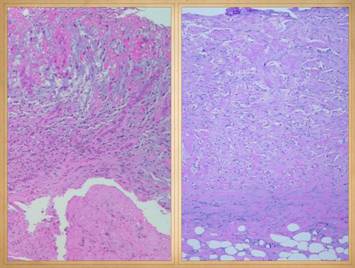

Left, a microscope image of normal wound healing.  The structure shown here is the prototypical wound.  Details of the structure and process will be explained in following panels.  Right, the microscopic appearance of fully regenerated Integra-CG matrix, the details likewise to be explained in following panels.  Even without explaining or focusing on specific details, the dissimilarity of the two can be appreciated.  Angiocytes and fibroblasts, vessels and connectives – that is all there is to these two tissues.  However, by supplying different “rules” or “subroutines” for the interaction and assembly of these elements, two different biomaterials emerge.  The rules or routines are based on the circumstances, reaction-to-injury versus embryonic regeneration.  The results have very different physical properties and implications for daily life, functional adaptations, and potential need for ongoing medical care.